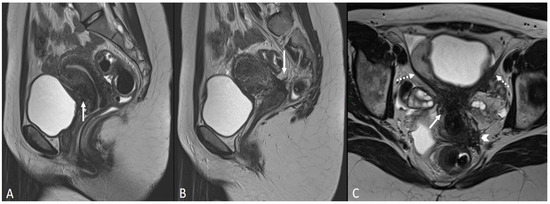

Figure 4.

Retrocervical endometriosis plaque, intestinal localization, kissing ovaries with bilateral ovarian endometriomas. (A,B) Axial T2WI; (C) Coronal T2WI. Hypointense retrocervical plaque (white arrowhead in (A)) localized in the uterine torus with involvement of the utero-sacral ligaments. Adhesions involve both ovaries with bilateral endometriomas (white arrows), which are prolapsed in a retro-uterine position and adhered to the utero-sacral ligaments and the recto-sigmoid junction. There is also an eccentric anterior parietal thickening in the recto-sigmoid junction suggestive of intestinal endometriosis lesion (white dotted arrow in (A)).